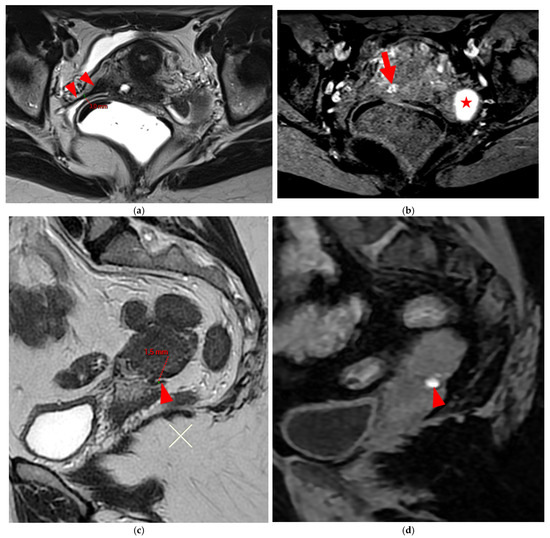

2.2.2. HTD Type 5 USL (PPV = 100%; FPR = 0%)

A type 5 USL appears nodular and can be classified either as type 5A or type 5B.

HTD Type 5A USL

A type 5A USL (Figure 6) is nodular with a smooth contour.

HTD Type 5B USL

A type 5B USL (Figure 7) is nodular with spiculated margins. A type 5B USL may also display an isolated nodule with microcystic content.

Figure 6. Pelvic MRI scans of two patients with HTD type 5A USLs. (a,b) Sagittal T2WI: nodularity with regular margins (arrows) within the right USL (arrowheads).

Diagnostics 15 01508 g006

Figure 7. Pelvic MRI scans of two patients with HTD type 5B USLs. (a) Patient 1: sagittal T2WI shows a microcystic nodule (arrow) within the origin of the right USL (arrowhead). (b,c) Patient 2: axial (b) and sagittal (c) T2WI show a nodular left USL with spiculated margins (arrow) and a right ovarian endometrioma (arrowhead).

Diagnostics 15 01508 g007